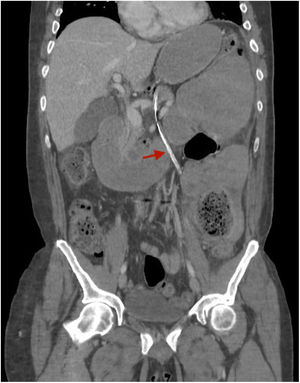

Varón de 46 años, con historia de múltitiples intervenciones abdominales, ingresado por oclusión intestinal. Se coloca sonda nasogástrica (SNG) que inicialmente no es productiva. Se solicita tomografía tóraco-abdominal por empeoramiento clínico, observándose un trayecto extraluminal de la SNG a nivel abdominal y torácico (fig. 1) sin hallar punto de perforación, y que se orienta como probable perforación a nivel cervical (fig. 2). La exploracion ORL identifica la perforación en cavum inferior, disecando la pared posterior de la faringe. Se retira la SNG, y se inicia tratamiento médico con corticoides, fluconazol y meropenem. El paciente presenta mejoría clínica radiológica e inicia tolerancia oral a la semana.